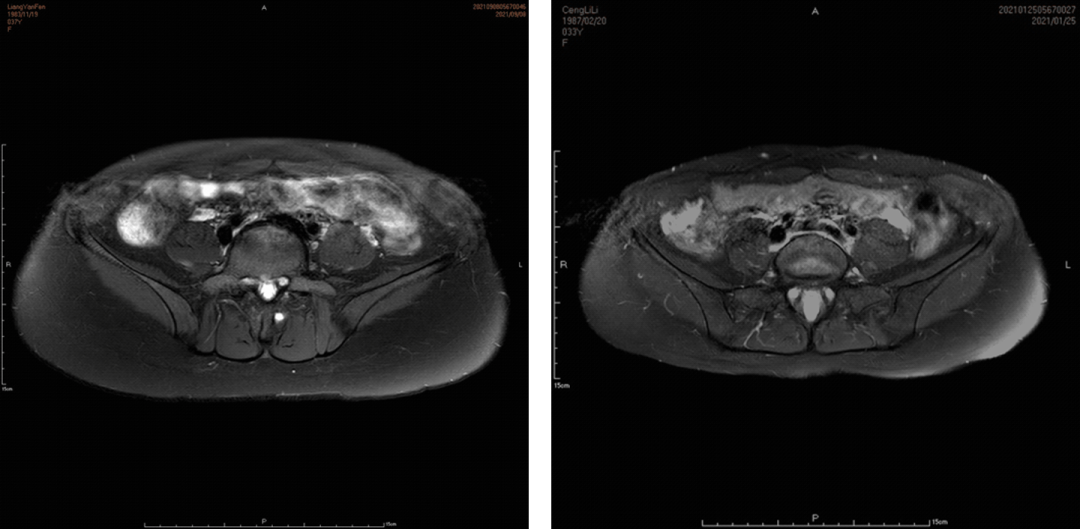

彩色多普勒超声:首选检查,“彩盘蛇”征象提示反流。

CTV / MRV:提供详细解剖结构,指导手术规划。

PeVD-髂内静脉同期栓塞

症状性PEP需要同期处理

示例(D-IIV)

示例(LOV+LCV)